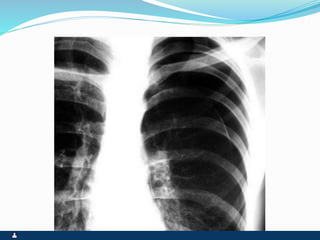

PNEUMOTÓRAX

RUPTURA DE UM DOS FOLHETOS

SINTOMAS SINAIS

 PRIMÁRIO ( ESPONTÂNEO

) SECUNDÁRIO(

TRAUMA,IATROGÊNICO )

 INÍCIO SÚBITO

 DOR PLEURÍCA INTENSA

 TOSSE SECA

 DISPNÉIA

 FACIES DE DOENÇA

AGUDA,ANSIEDADE E

SUDORESE

 EXPANSIBILIDADE REDUZIDA

 DESVIO CONTRALATERAL DO

MEDIASTINO

 ABAULAMENTO

HOMOLATERAL DOS

ESPAÇOS INTERCOSTAIS

 FTV ABOLIDO

 TIMPANISMO

 MV ABOLIDO

 RUIDOS ADVENTÍCIOS

AUSENTES

 ENFISEMA SUBCUTÂNEO

EVENTUAL